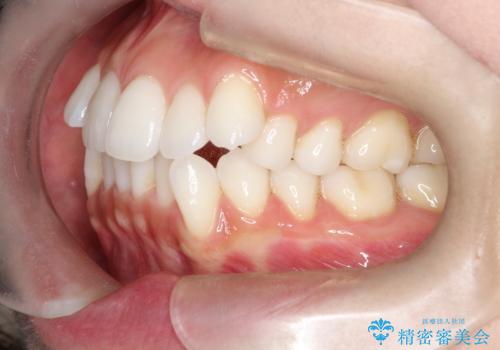

- 患者さんは「口元を引っ込めたい」「八重歯をきれいにしたい」とのご希望で来院されました。診察の結果、上下の前歯が前方に傾斜し、口元がやや突出して見える状態でした。加えて、上顎には八重歯があり、歯列のスペース不足も確認されました。

歯並びと横顔のバランスを整えるためには、前歯を後方に移動させるスペースの確保が必要です。そのため、上下左右の第一小臼歯(合計4本)を抜歯し、ワイヤー矯正で前歯の突出感と叢生(がたつき)を同時に改善する治療計画を立てました。歯を抜くことに抵抗がある方も多いですが、口元の印象を変えるためには非常に効果的な方法です。